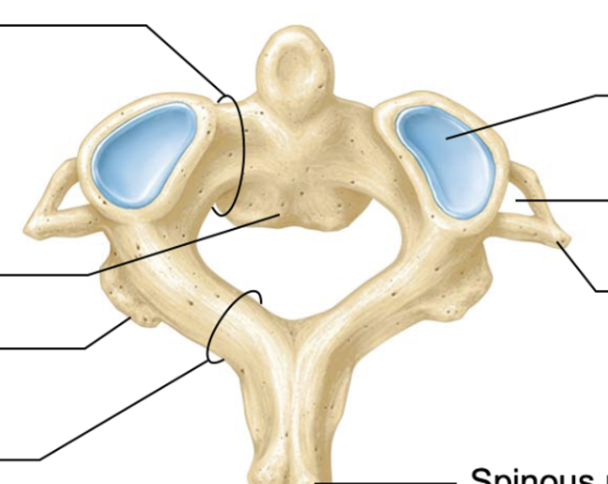

Vertebral foramen

opening/hole where spinal cord passes through

Atlas cervical vertebra

No vertebrae body

No spinous process

Still contains transverse foramen

Allows us to shake out head yes

Axis cervical vertebra

allows us to shake our head no

thoracic vertebrae

lumbar vertebrae